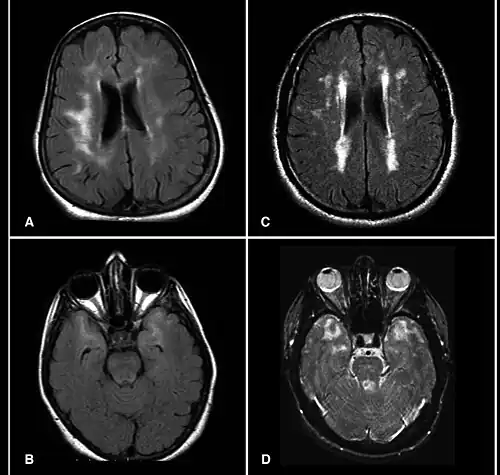

MRI scans showing hyperintensities

A hyperintensity or T2 hyperintensity is an area of high intensity on types of magnetic resonance imaging (MRI) scans of the brain of a human or of another mammal that reflect lesions produced largely by demyelination and axonal loss. These small regions of high intensity are observed on T2 weighted MRI images (typically created using 3D FLAIR) within cerebral white matter (white matter lesions, white matter hyperintensities or WMH)[1][2] or subcortical gray matter (gray matter hyperintensities or GMH). The volume and frequency is strongly associated with increasing age.[2] They are also seen in a number of neurological disorders and psychiatric illnesses. For example, deep white matter hyperintensities are 2.5 to 3 times more likely to occur in bipolar disorder and major depressive disorder than control subjects.[3][4] WMH volume, calculated as a potential diagnostic measure, has been shown to correlate to certain cognitive factors.[5] Hyperintensities appear as "bright signals" (bright areas) on an MRI image and the term "bright signal" is occasionally used as a synonym for a hyperintensity.

Hyperintensities are commonly divided into 3 types depending on the region of the brain where they are found. Deep white matter hyperintensities occur deep within white matter, periventricular white matter hyperintensities occur adjacent to the lateral ventricles and subcortical hyperintensities occur in the basal ganglia.